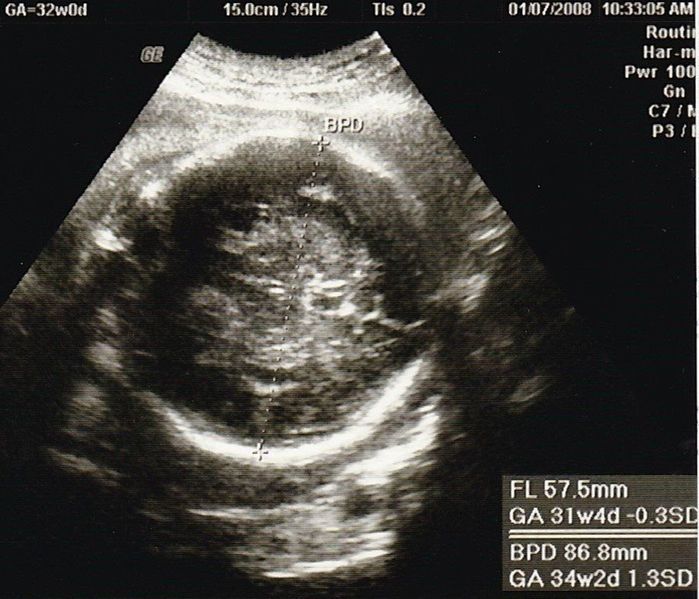

妊娠32週目のエコー写真

2000gを超えました。安心と同時に、体の重い状態がまだあと2カ月も続き、まだ大きくなるのかと思うと少し憂鬱に。体重も7kg以上増え助産師さんに注意されたものの、何か口に入れていないと気持ち悪くなるような状態で、つい食べ過ぎて自己嫌悪になることもありました。